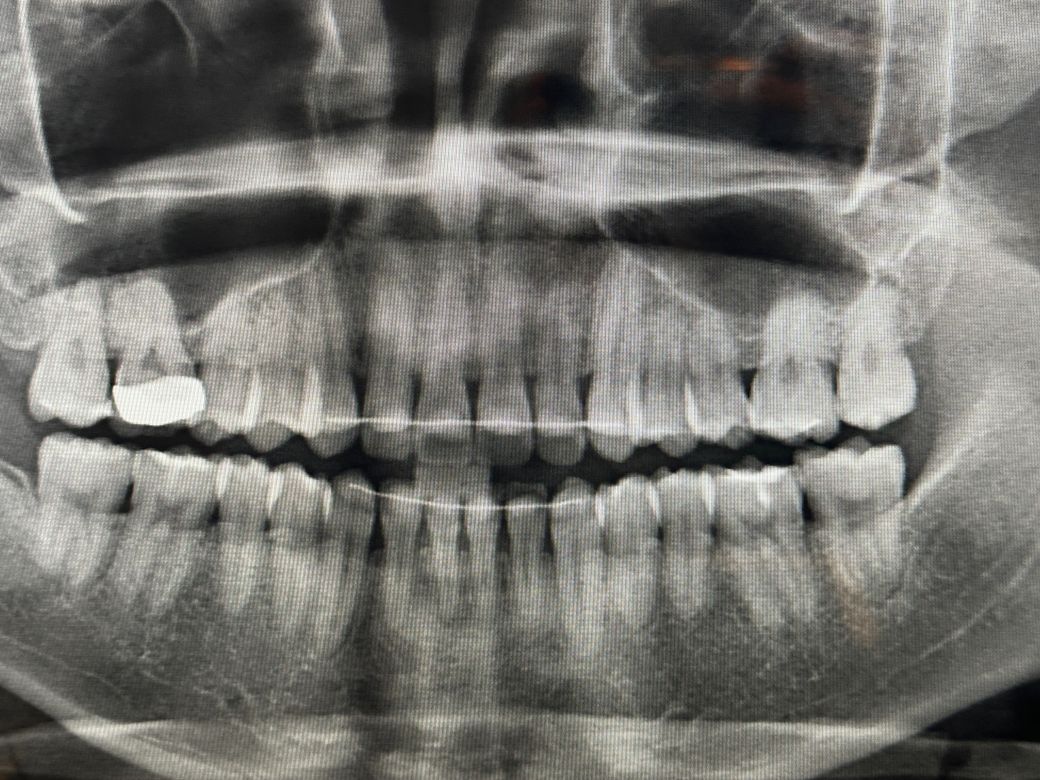

이거 인접면 충치인가요? 여러군데 갔는데 헷갈려요

오른쪽 상악 어금니인데 총 3군데 치과를 갔습니다 원래 1면전부터 이부분에 깨진면이 있었습니다 이 부분을 첫번째 치과에서 바이트윙 찍고 인접면 충치가 있어서 신경치료 가능성까지 언급하시더라고요 그래서 두번째 치과를 갔는데 육안이랑 파노라마까지만 보시고 없다고 깨진부분만 레진으로 떼워주셨어요 그래도 미심쩍어서 세번째 치과갔는데 여기는 이 파노라마랑 육안에 넣고보는 카메라로 보셨는데 여기도 없다고 하시더라고요 첫번째 같이 심한데 두곳이 모른걸까요 아니면 별로 없는것 같나여 보기에는 둘다 맞아보여서 질문합니다

• 1번 째 사진

1. 충치가 있는것은 맞습니다. 원래 인접면 우식의 경우 교합면보다 신경과 거리가 짧기 때문에 신경치료 가능성은 루틴하게 언급됩니다.

3. 해당 부위 충치가 생긴 건 아무래도 그 앞 크라운의 마진이 아주 핏하게 맞지 않기 때문입니다. 그 사이로 계속 침과 음식물이 끼어 들어가니 충치가 생길 수 밖에 없죠. 평소에도 본인이 해당 부위 음식물이 잘 낀다고 느꼈다면 크라운 재제작을 하여 문제를 적극적으로 해결하거나 아니면 적어도 해당 부위 치실이나 치간칫솔로 아주 꼼꼼하게 관리해주셔야 합니다.

일단 바이트 윙 사진에서는 인접면 충치가 없어 보입니다 두번째 치과에서 파노라마 찍고 레진 치료 하신 거 같고 세번째 치과에서 눈으로 보시니 인접면 충치가 없고 레진 치료까지 했으니 정상이라고 한거 같습니다 아무튼 현재 상태는 이제 정상 소견 같아 보이니 너무 걱정 않으셨으면 합니다